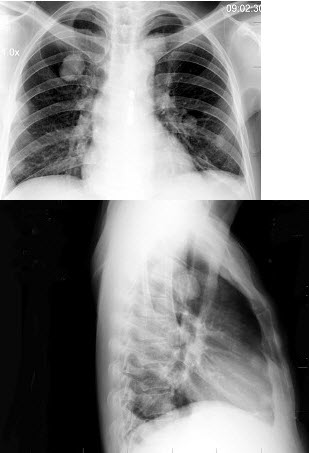

6、单项选择题

男,38岁,咳嗽、胸痛、咯血1天,X线检查如图,最可能的诊断是()

A.炎性假瘤

B.原发性肺癌

C.肺结核球

D.肺转移瘤

E.结节病